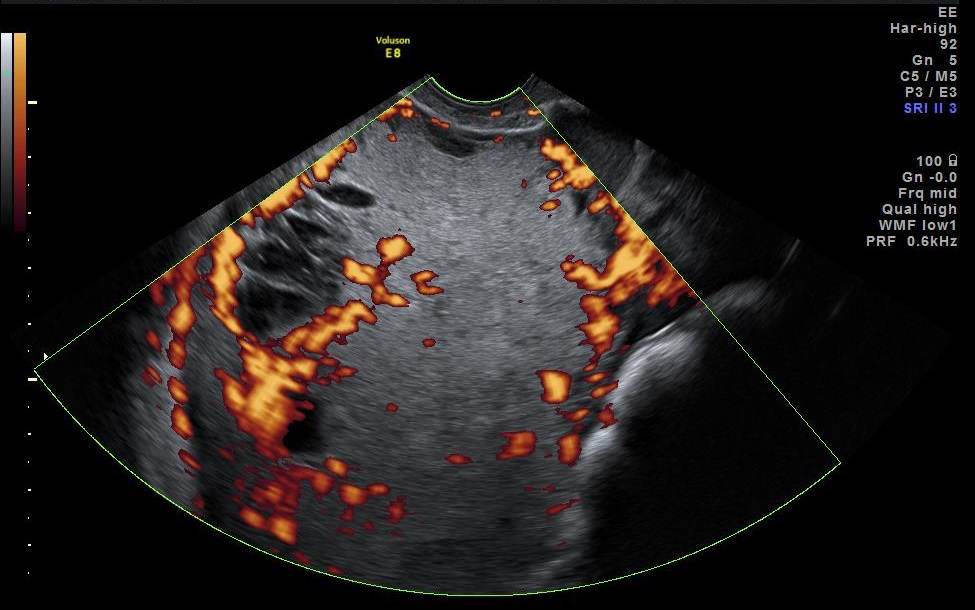

Granulosacellstumörer producerar ofta östrogen och förekommer hos kvinnor i alla åldrar. I en serie på 23 fall beskrivs tumören som ensidig, solid eller flerrummigt solid (många gånger solid med små cystiska hålrum, s.k. ”schweizerost”). Den har rikligt blodflöde och oregelbunden ekogenicitet med en medeldiameter på 10 cm3. Se bild 5.

Bild 5. Granulosacellstumör hos 30-årig kvinna med blödningsrubbningar och infertilitet.